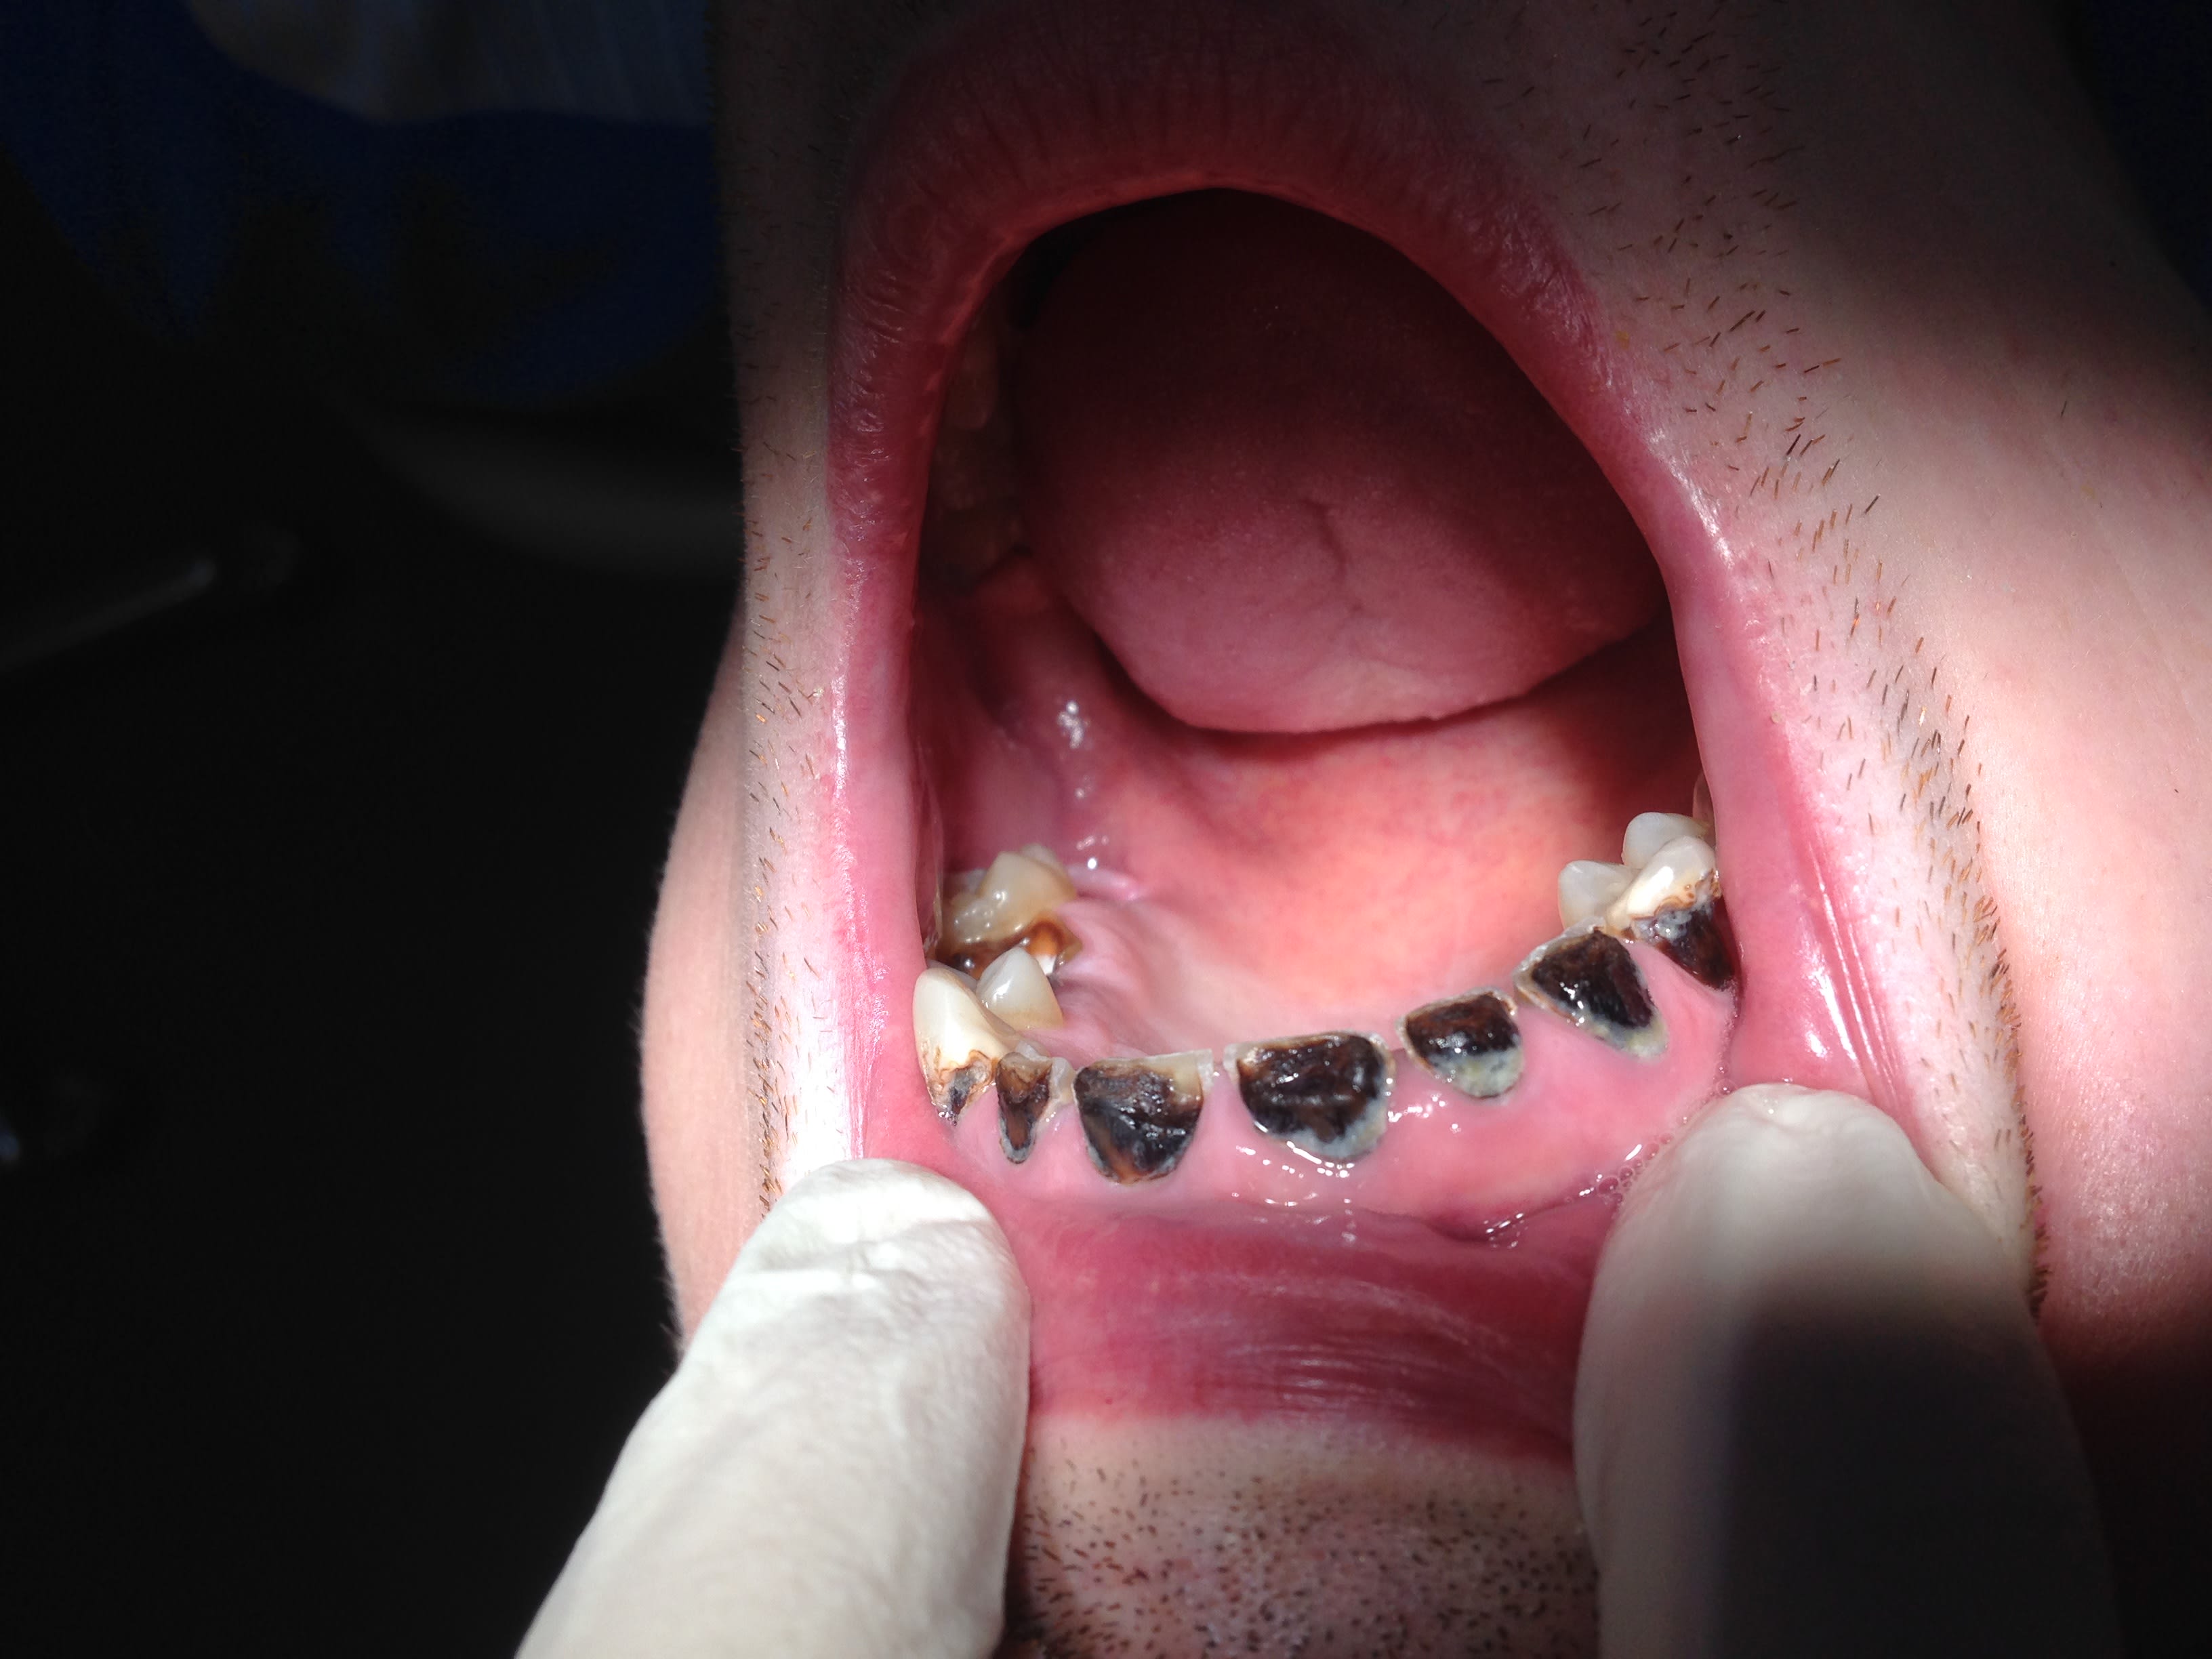

et celui là tu crois qu'il a fait quoi ? 😊Il a la 20aine

Y a maman des beaux quartiers qui va lui payer toutes les prothèses